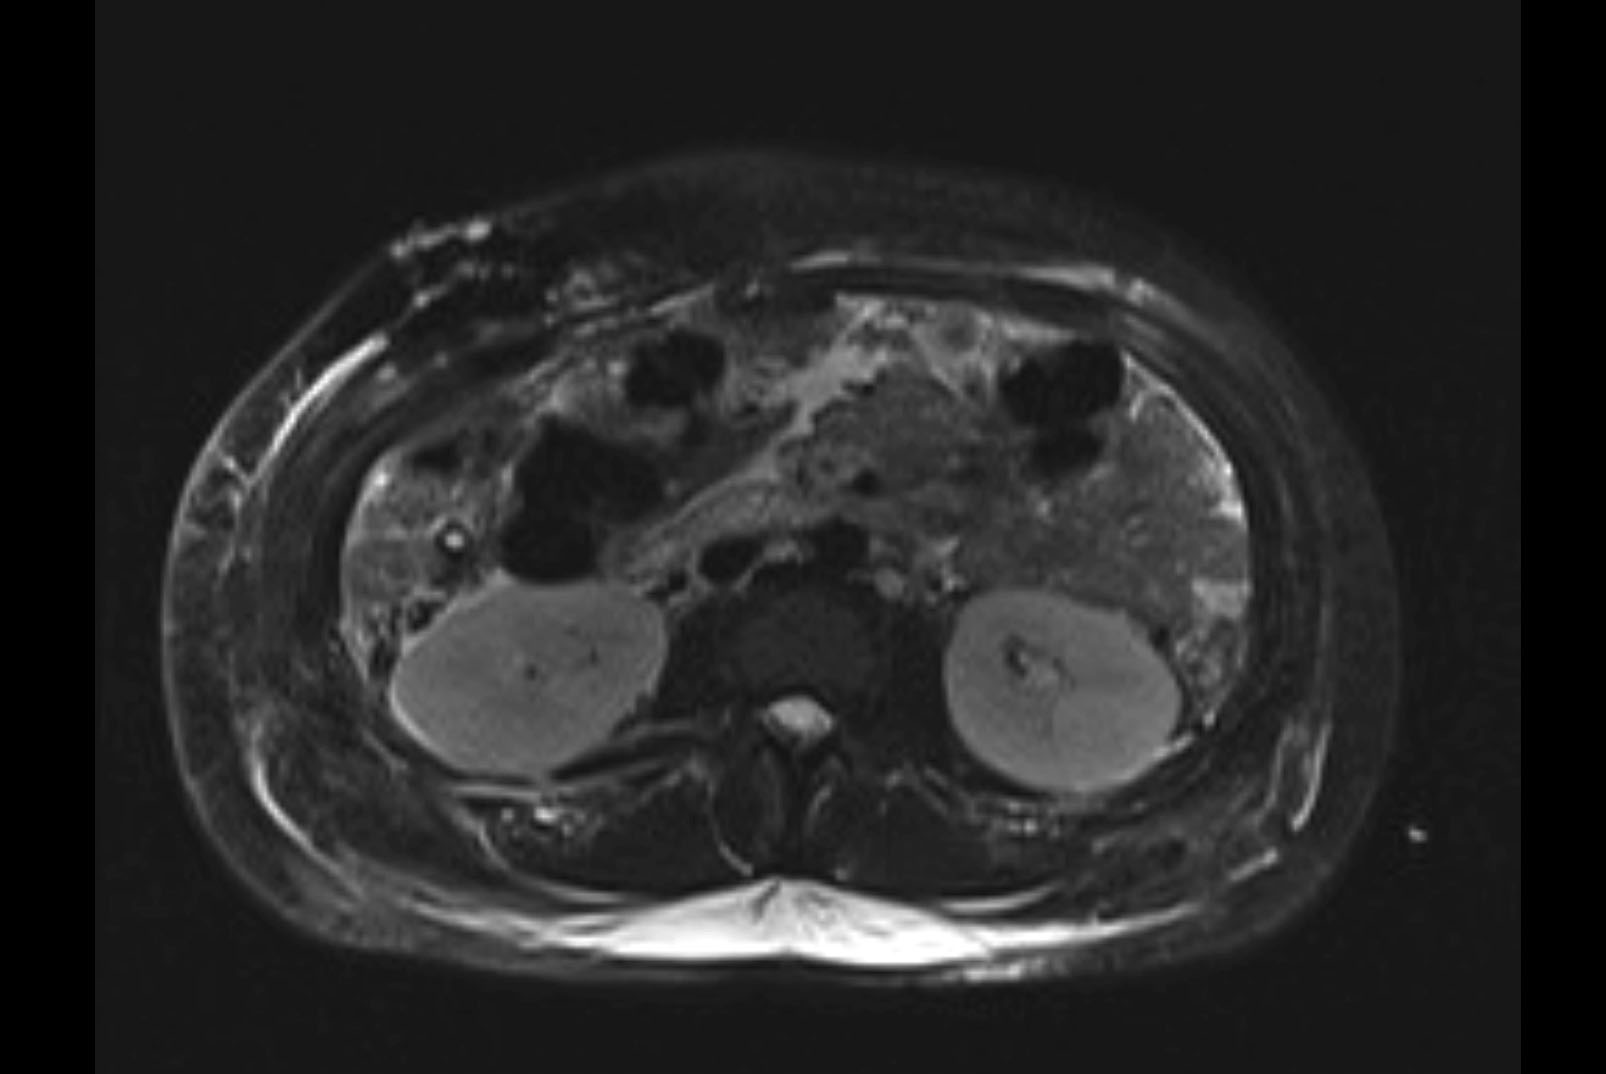

Imaging Analysis

Look through the patient's CT scan to identify any areas of concern for the necessary procedure.

MRI T2

Based on initial findings, which issue(s) would you be most concerned about?